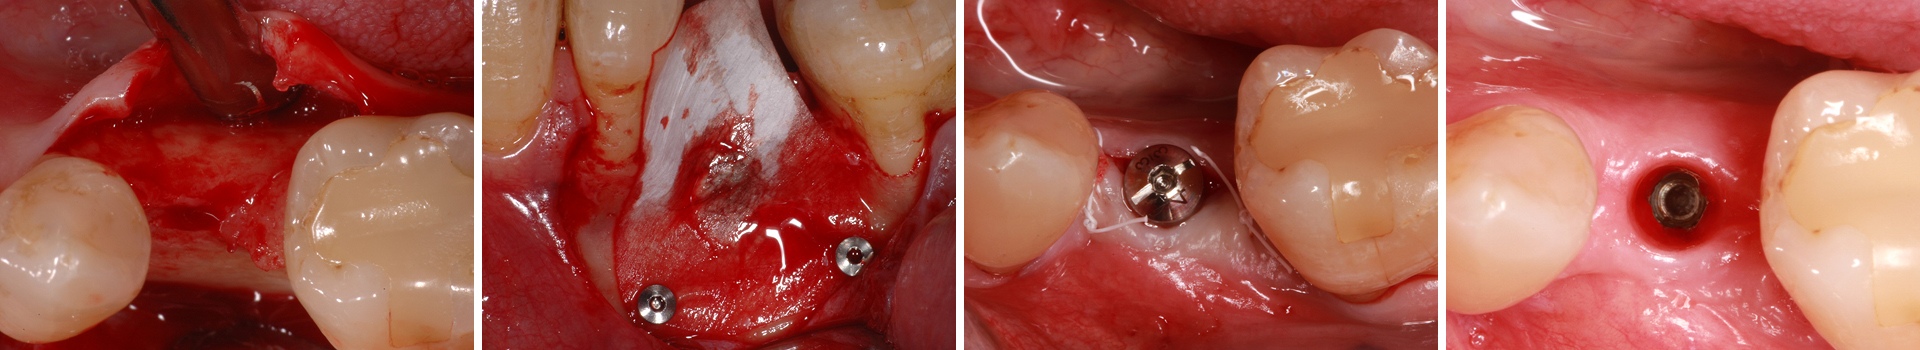

Abbildung 2

Simultane Implantation und GBR: Darstellung des späteren Implantatlagers nach Elevation eines Mukoperiostlappens; es zeigt sich ein horizontal ungenügendes Knochenangebot.

Abbildung 3

Okklusale Ansicht nach Insertion eines 4 mm-Implantats mit Plattform-Switching. Eine simultane Defektrekonstruktion erscheint möglich.

Abbildung 4

In der Lateralansicht zeigt sich ein moderater Dehiszenzdefekt bei gut erhaltener Knochenstruktur an den Nachbarzähnen, welche die Knochenregeneration unterstützen werden.